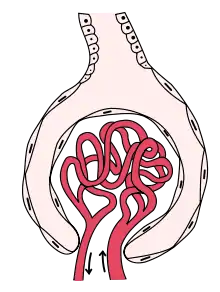

The renal corpuscle is the site of the filtration of blood plasma. The renal corpuscle consists of the glomerulus, and the glomerular capsule or Bowman's capsule.[3]: 1027

The renal corpuscle has two poles: a vascular pole and a tubular pole.[4]: 397 The arterioles from the renal circulation enter and leave the glomerulus at the vascular pole. The glomerular filtrate leaves the Bowman's capsule at the renal tubule at the urinary pole.

Glomerulus

The glomerulus is the network known as a tuft, of filtering capillaries located at the vascular pole of the renal corpuscle in Bowman's capsule. Each glomerulus receives its blood supply from an afferent arteriole of the renal circulation. The glomerular blood pressure provides the driving force for water and solutes to be filtered out of the blood plasma, and into the interior of Bowman's capsule, called Bowman's space.

Only about a fifth of the plasma is filtered in the glomerulus. The rest passes into an efferent arteriole. The diameter of the efferent arteriole is smaller than that of the afferent, and this difference increases the hydrostatic pressure in the glomerulus.

Bowman's capsule

The Bowman's capsule, also called the glomerular capsule, surrounds the glomerulus. It is composed of a visceral inner layer formed by specialized cells called podocytes, and a parietal outer layer composed of simple squamous epithelium. Fluids from blood in the glomerulus are ultrafiltered through several layers, resulting in what is known as the filtrate.